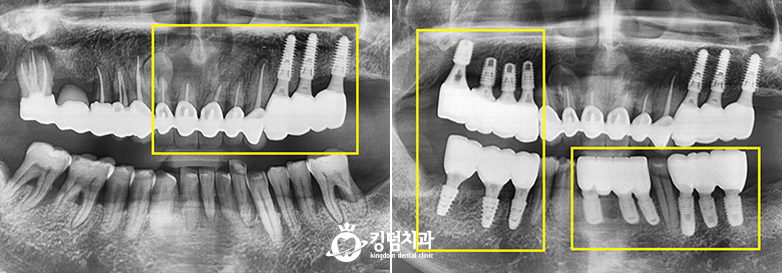

• 킹덤치과 전후사진

• 잇몸뼈 녹음, 2차 충치

• Before After